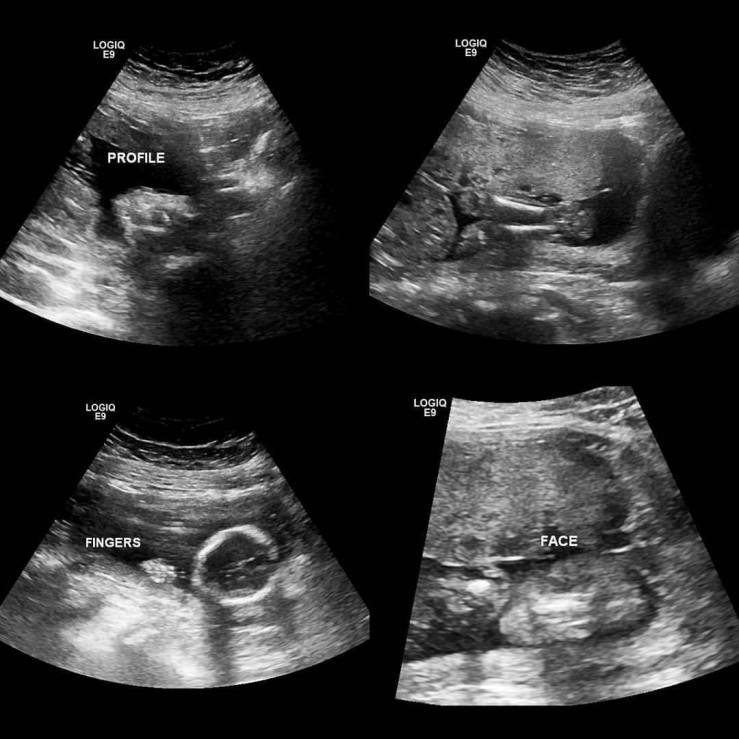

Our 20 week ultrasound was awesome. We got to see brother & he’s happy & healthy. He was moving around so fast we didn’t get a great image of his cute little profile. But here are a few of our favorites!